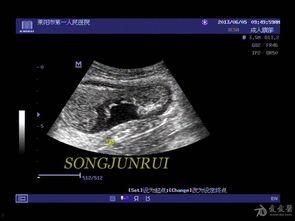

正常情况下,肠壁会不断地蠕动,帮助消化食物。但肠梗阻发生时,肠壁蠕动会减弱,甚至停止。在超声检查中,你可以看到肠壁蠕动波不明显,或者根本看不到。

肠梗阻还会压迫肠系膜血管,导致血流受阻。在超声检查中,你可以看到肠系膜血管血流信号减弱,甚至消失。

在这段视频中,你可以看到:

- 肠壁蠕动减弱,蠕动波不明显;

- 肠系膜血管受压,血流信号减弱。